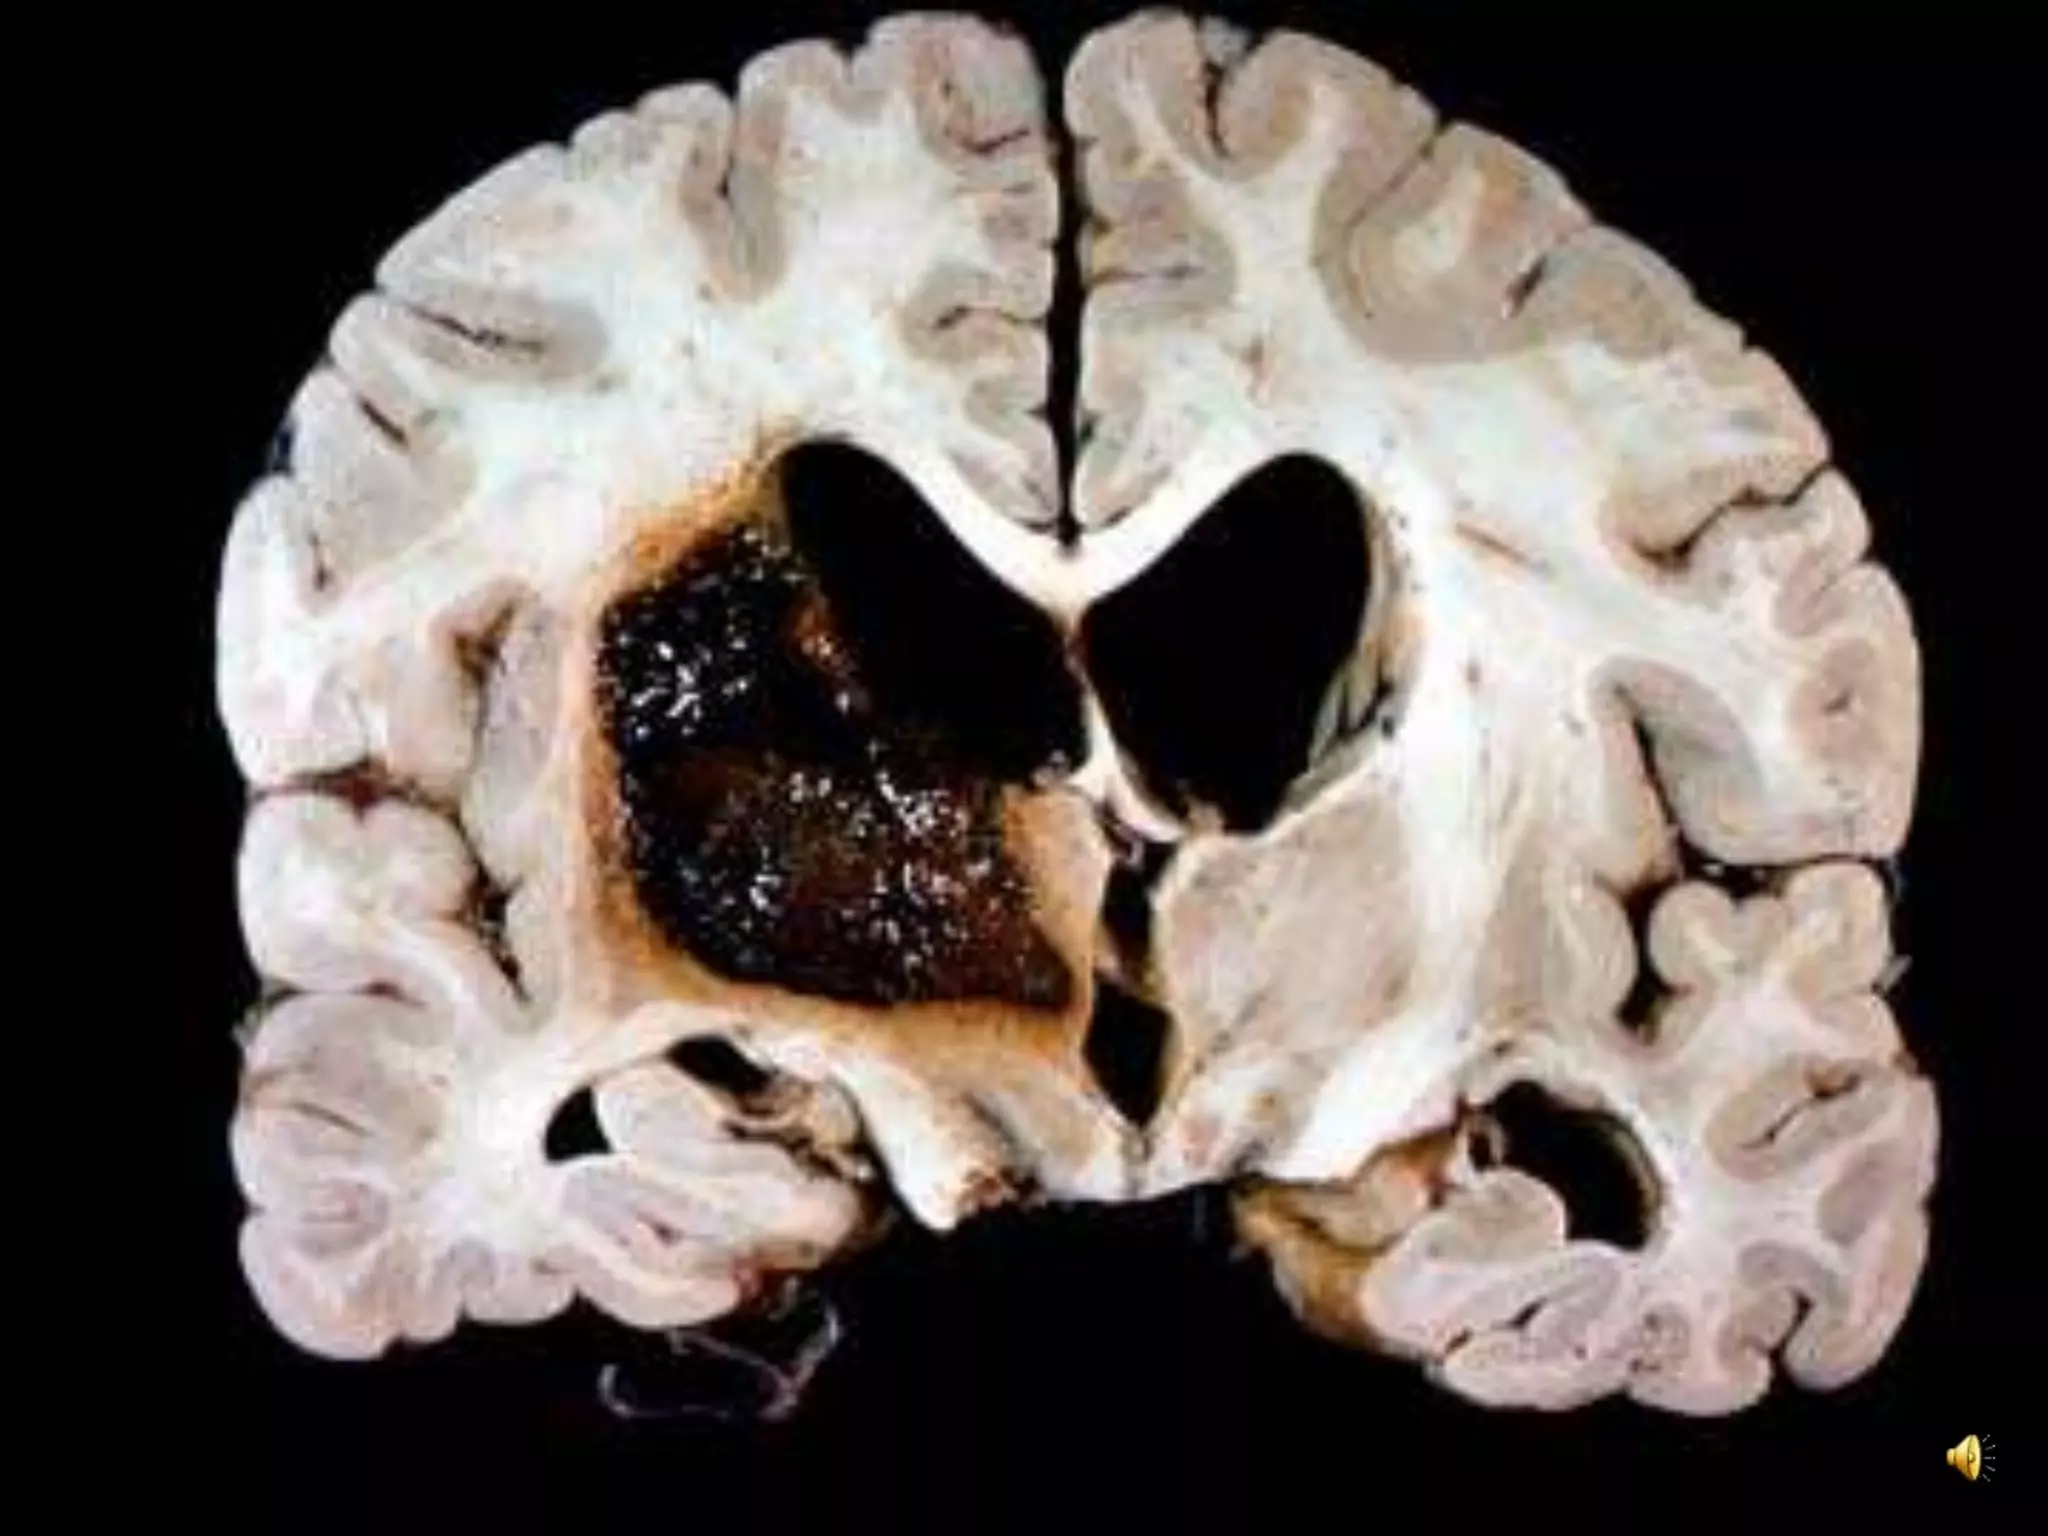

Diagnosis: Recent cerebral infarction in left MCA distribution.

Left cerebral hemisphere shows swelling with compression of the lateral ventricle

mainly in the frontal area, due to recent infarct in the Middle Cerebral Artery (MCA)

distribution. The brain in the MCA area shows discoloration of the cortex and also

blurring between the cortex and white matter.

Left(Dominant)HemisphereStroke:Clinical • Aphasia • Righthemiparesis • Right-sided sensory loss • Right visual field defect • Poor right conjugate gaze • Dysarthria • Difficulty reading, writing, or calculating Diagnosis: Recent cerebral infarction in left MCA distribution. Left cerebral hemisphere shows swelling with compression of the lateral ventricle mainly in the frontal area, due to recent infarct in the Middle Cerebral Artery (MCA) distribution. The brain in the MCA area shows discoloration of the cortex and also blurring between the cortex and white matter.